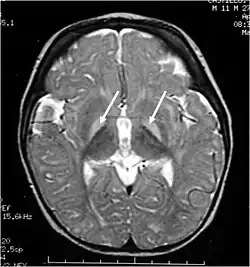

| Brain MRI. Hyperintense basal ganglia lesions on T2-weighted images, showing Kernicterus bilirubin encephalopathy. | |

Kernicterus, is accumulation of high levels of unconjugated bilirubin within the basal ganglia of brain which can cause neurological lesions. Reduction of bilirubin in this state will not reverse the sequelae.[4] Christian Georg Schmorl coined the term Kernicterus in 1904.

These impairments are associated with lesions in the basal ganglia, auditory nuclei of the brain stem, and oculomotor nuclei of the brain stem. Cortex and white matter are subtly involved. Cerebellum may be involved. Severe cortical involvement is uncommon.